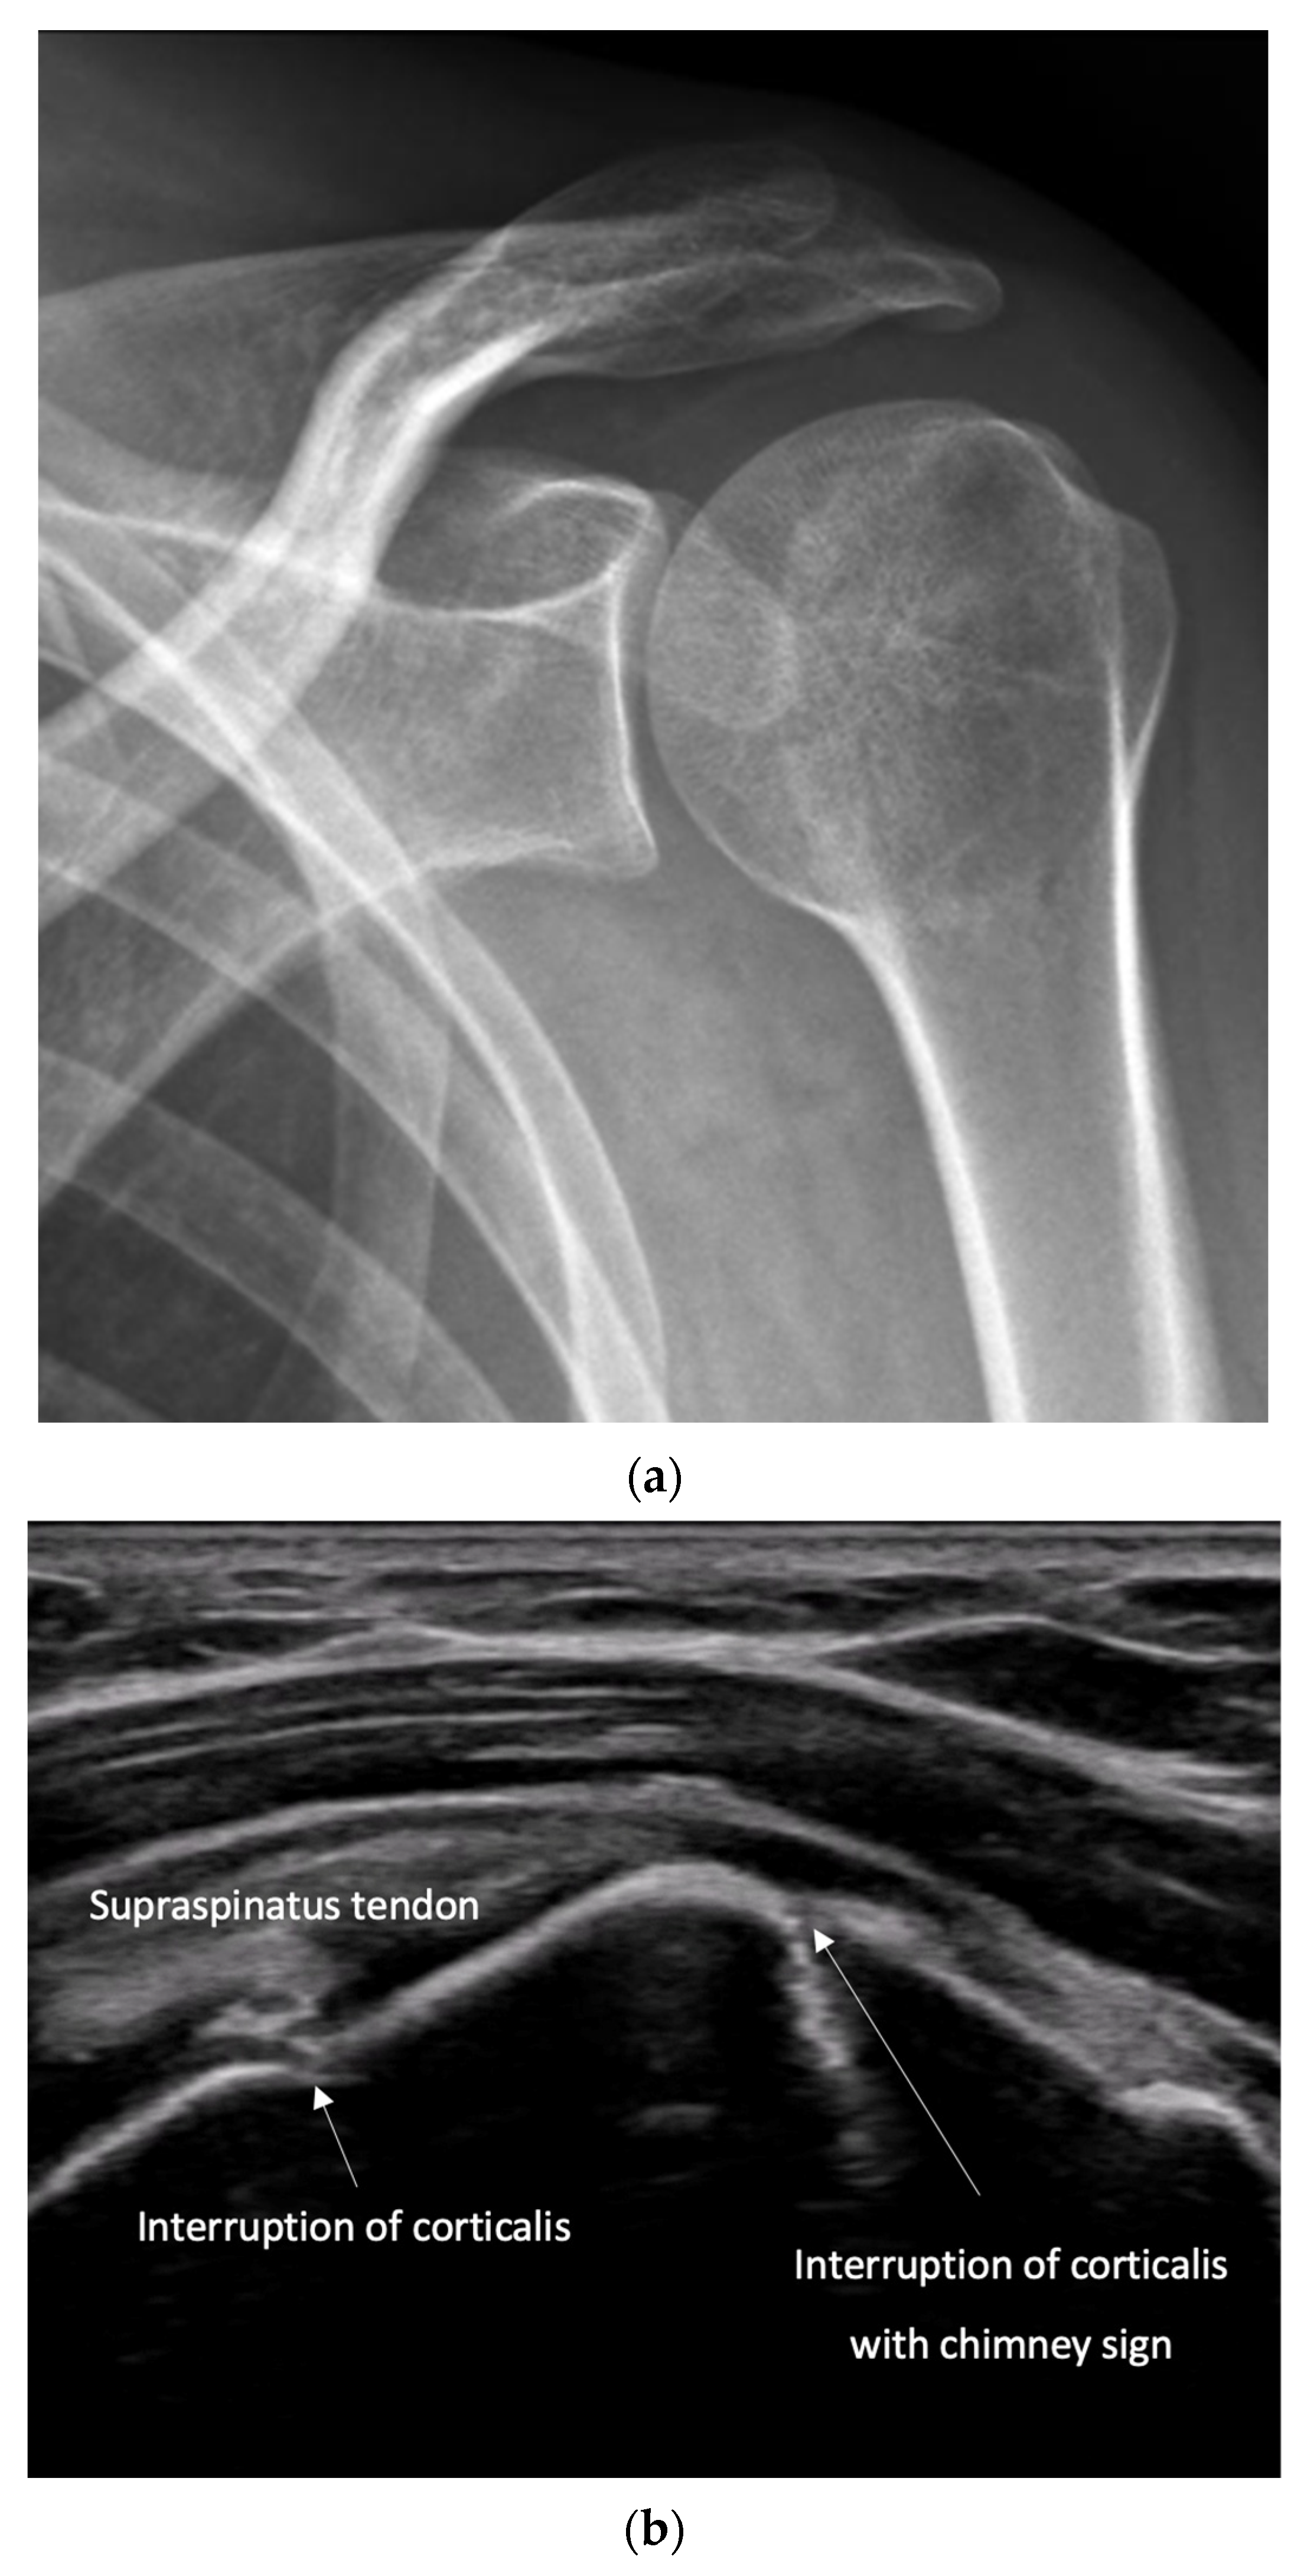

4.2. Sonoanatomy of Fractures [Figure 5, Figure 6, Figure 7 and Figure 8]

- Irregularity, interruption, or gaps in the cortical line: the cortical bone normally appears as a continuous, bright echogenic line, which is interrupted or irregular in the presence of a fracture.

- Reverberation artifacts within or adjacent to the fracture gap (also known as the “chimney sign”): these repetitive echoes are caused by ultrasound waves reflecting off the fracture surfaces.

- Quick exclusion of fractures in shoulder dislocations for timely reduction (Figure 13).

- Recommendation 6: Ultrasound should be integrated into the assessment and management of shoulder injuries, including proximal humerus fractures, shoulder dislocations, and post-relocation maneuvers, both prehospitally, in emergency departments, and other acute care settings.